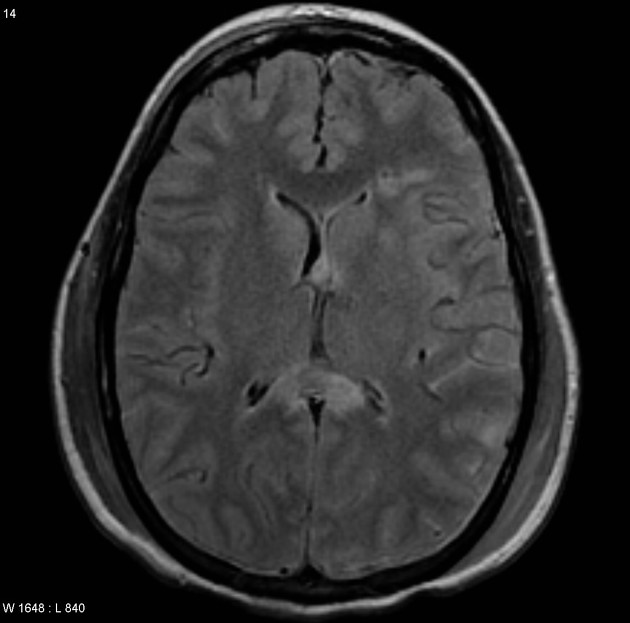

Multiple Lésions punctiformes bilatérales de topographie évocatrice. Examen a visé pronostic à réaliser dans les 7 jours.

-T1 : hypersignal T1 des lésions pétéchiales hémorragiques. -T2 : Lésions pétéchiales hémorragiques de signal variable (dégradation de l’hémoglobine)

Lésion non hémorragiques en Hypersignal T2 -T2 EG : hyposignal des lésions pétéchiales hémorragiques (susceptibilité magnétique). - SWAN/SWI : Imagerie de susceptible magnétique haute résolution. pétechies +++ -Diffusion (+/- Tractographie): Foyers punctiformes en hypersignal diffusion - restriction ADC.